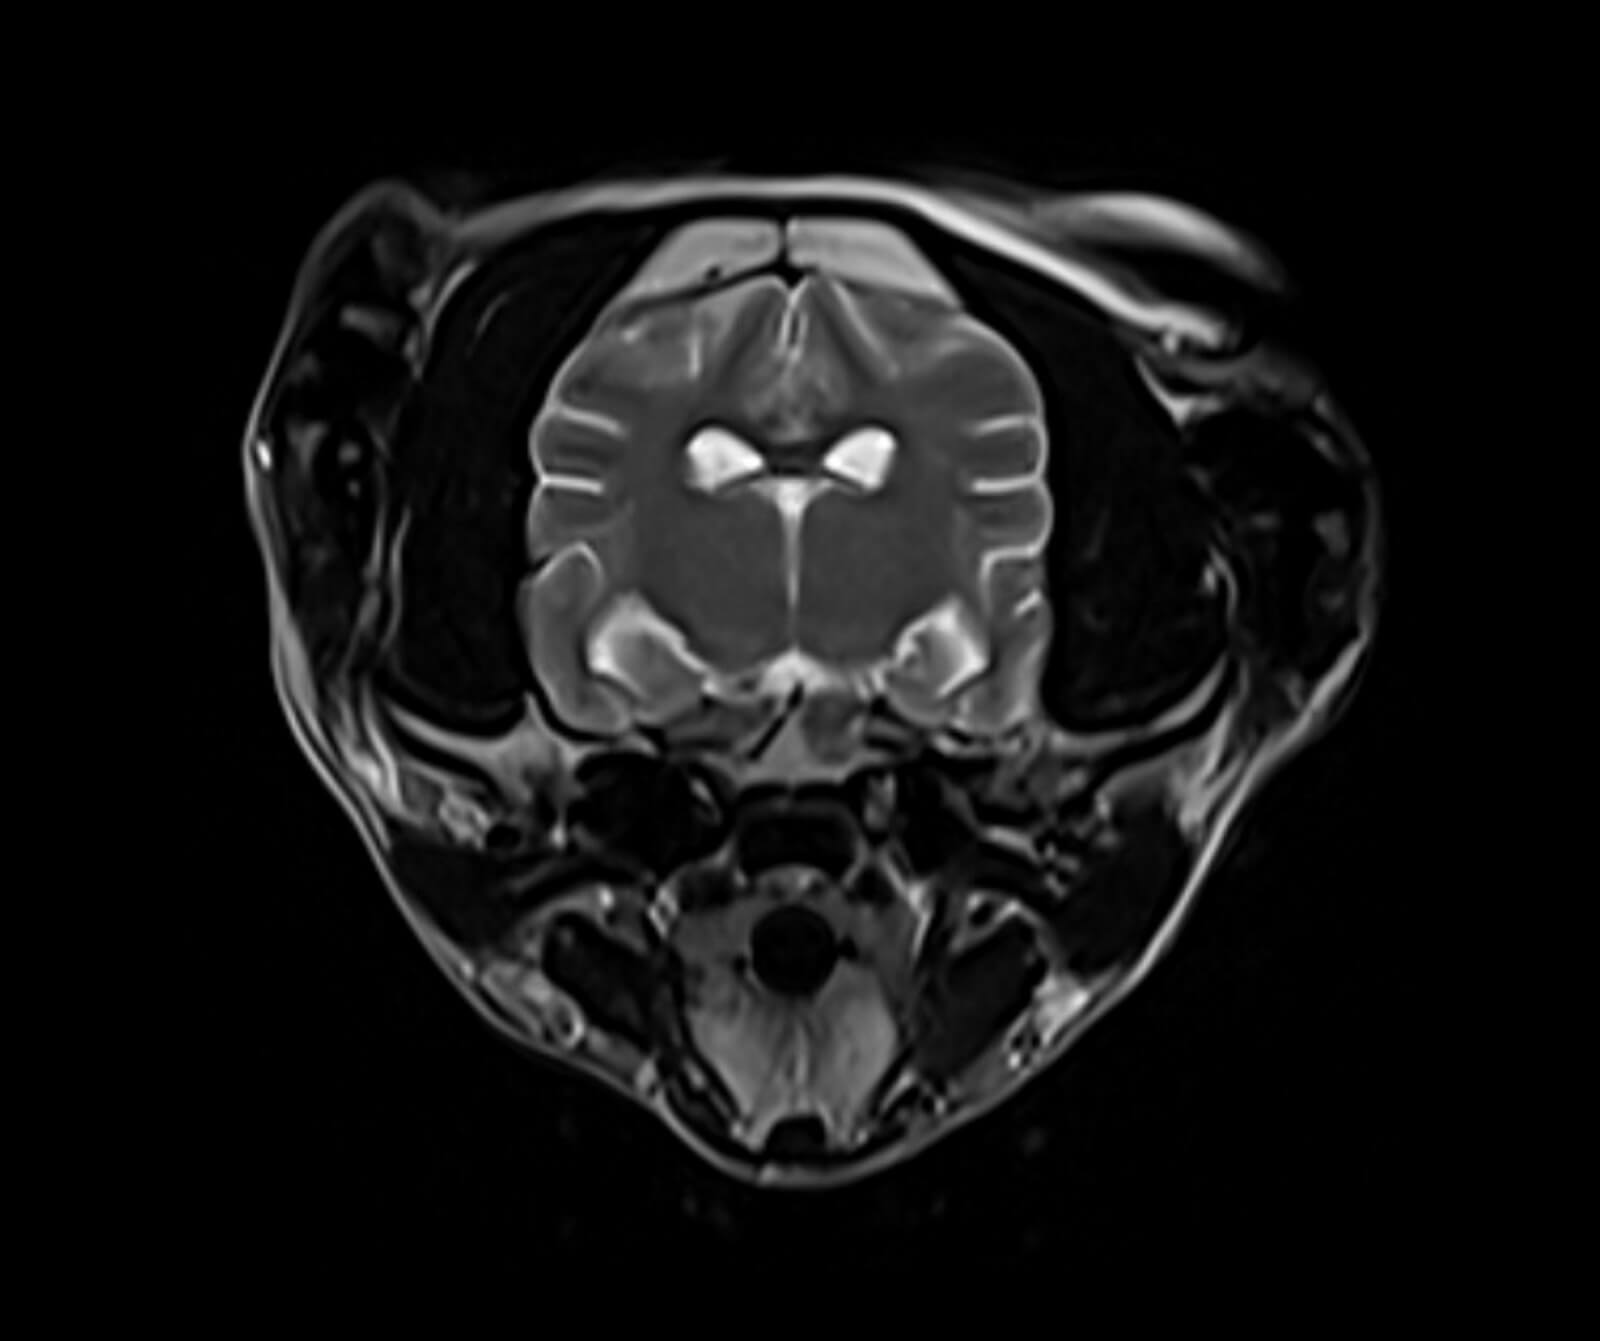

Manyetik Rezonans Görüntüleme (MR), sevimli dostlarımızın vücudundaki doku ve organların yüksek çözünürlükte, ayrıntılı ve güvenli biçimde değerlendirilmesini sağlayan ileri düzey bir tanısal görüntüleme yöntemidir. Radyasyon içermeyen bu yöntem, özellikle yumuşak dokuların detaylı incelenmesi gereken durumlarda en değerli tanı araçlarından biridir.

Veteriner hekimliğinde MR; beyin, omurilik, sinir sistemi, kas-iskelet sistemi ve iç organ hastalıklarının değerlendirilmesinde kritik rol oynar. Kemik yapılar dâhil olmak üzere vücudun tüm bölgeleri MR ile ayrıntılı şekilde incelenebilir.

• Beyin ve nörolojik hastalıkların değerlendirilmesi

• Tümörler, felç, beyin kanamaları ve damar tıkanıklıkları